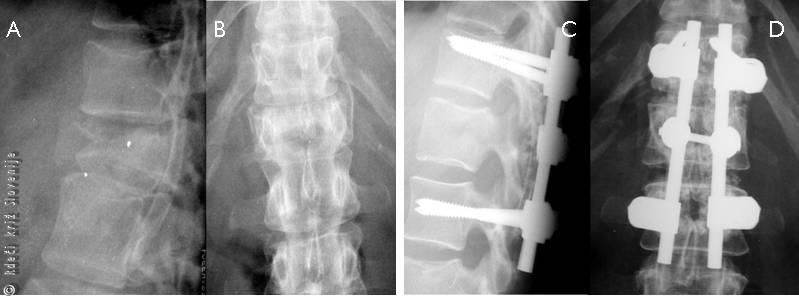

Večina poškodb hrbtenice je blažjih in se lahko zdravi konzervativno. Hujše poškodbe, predvsem tiste z večjo nestabilnostjo ali celo premikom poškodovanih segmentov, pa se zdravijo z operativno naravnavo oz. stabilizacijo. Ob tem je operacija namenjena predvsem stabilizaciji skeletnih elementov, zmanjšanju utesnitve in s tem preprečitvi morebitnih nadaljnjih ali kasnejših poškodb živčnih struktur, ter tako boljšim pogojem za hitrejšo rehabilitacijo in okrevanje. Na žalost še vedno velja, da je izboljšanje v primeru kompletnih nevroloških izpadov, ki nastopijo takoj ob poškodbi, najpogosteje minimalno oz. ga ni! Tudi zato je pravilno ravnanje pri pristopu k poškodovancem velikega pomena!

Slika 9

Zlom (A, B) in stanje po operativni stabilizaciji skeleta (C, D).

50-letni ženski se je pri obiranju češenj zlomila veja in padla je 5 m v globino. Na tla je priletela na zadnjico. Takoj je začutila hudo bolečino v hrbtu, ki je bila tako huda, da ni mogla več vstati. Svojci so poklicali reševalni avtomobil, ki jo je odpeljal v bolnišnico. Tam so ugotovili zlom prvega ledvenega vretenca, lahko pa je gibala s spodnjima udoma in normalno čutila dotik na spodnjih udih. Zaradi zloma je bila potrebna operativna stabilizacija, po dveh tednih pa je začela z rehabilitacijo. Na svoje delovno mesto (kjer ni potrebno dvigovanje ali prenašanje težjih bremen) se je vrnila čez pol leta.